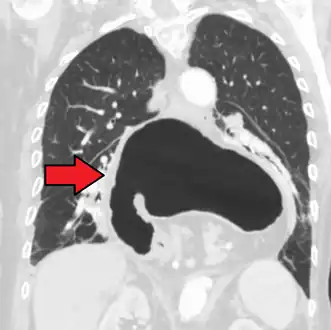

Diagnosis

The diagnosis of a hiatal hernia is typically made through an upper GI series, endoscopy, high resolution manometry, esophageal pH monitoring, and computed tomography (CT). Barium swallow as in upper GI series allows the size, location, stricture, stenosis of oesophagus to be seen. It can also evaluate the oesophageal movements. Endoscopy can analyse the esophageal internal surface for erosions, ulcers, and tumours.

Meanwhile, manometry can determine the integrity of esophageal movements, and the presence of esophageal achalasia. pH testings allows the quantitative analysis of acid reflux episodes. CT scan is useful in diagnosing complications of hiatal hernia such as gastric volvulus, perforation, pneumoperitoneum, and pneumomediastinum.[8]